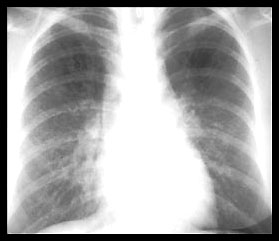

STAGE III STAGE IV

Permanent lung fibrosis. ( 20% )